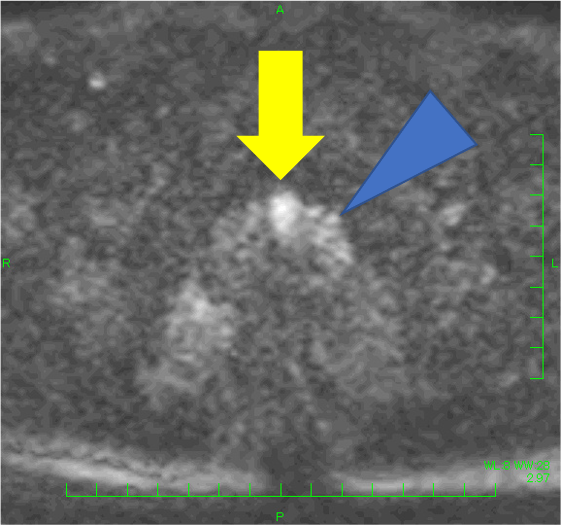

検診でPSA 4.9と上昇があり、MRIが施行された。左移行域に14mmの病変を認め、T2強調像で低信号(PI-RADS v2.1スコア4)、拡散強調像で高信号・Appar-ent Diffusion Coefficient(ADC)低下(スコア4)、ダイナミックで早期濃染を示し、PI-RADS v2.1でカテゴリー4と判定され前立腺癌が疑われた。一方、辺縁域はT2強調像で不均一低信号を呈したが、結節様の拡散強調像での強い高信号、ADC低下はなく、ダイナミックMRIでも結節様の早期濃染はなく、びまん性遷延性の染まりがみられたことから炎症性変化と判断した。生検が行われ、癌の診断であった。その後、ロボット支援下根治的前立腺摘除術が施行され、MRIと一致した前立腺癌の診断を得た(Gleason score 4+3=7, pT2N0)。

本症例では、左移行域腹側の病変(14mm、T2強調像:低信号(スコア4)、拡散強調像:高信号・ADC:低下(スコア4)、ダイナミック:早期濃染: PI-RADS v2.1カテゴリー4)は、前立腺癌の判定が容易であった。一方、辺縁域はT2強調像でびまん性に不均一な低信号を呈し、癌の評価が難しい方であった。左辺縁域に小結節様のT2強調像にて低信号がみられ、拡散強調像やADCの所見は明瞭でなく癌の可能性は低いと考えたが、T2強調像での信号が明瞭で、癌を否定してよいのか悩ましい。本症例では、ダイナミックMRIも施行しており、左移行域腹側病変は早期濃染―washout パターンを呈したが、左辺縁域の小結節に早期濃染はなく、両側辺縁域とも遷延性の染まりを認めたため、辺縁域に癌はなく、両側辺縁域に炎症性変化があると断定できた。病理的にも、MRIで指摘した病変部のみ癌が同定され、その他の領域に癌はなかった。